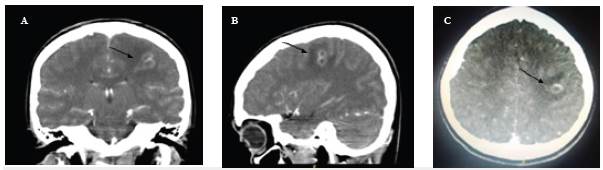

Una mujer de 19 años, que laboraba como mesera, ingresó al servicio de urgencias por presentar artralgia en rodilla derecha, asociada a vómito, y petequias, de 3 días de evolución (figura 1) así como hemiparesia derecha. Al examen físico presentaba signos vitales normales, petequias que no desaparecían a la digitopresión en manos, cara y dorso, además de pústulas en miembros inferiores con descamación de piel en regiones distales, y una hemiparesia derecha grado 3/5. Al ingreso se realizaron estudios paraclínicos (tabla 1) e imagenológicos. Se encontró hipo-densidad parietal subcortical izquierda macrolobulada en la tomografía computarizada (TC) simple y contrastada (figura 2), por lo que se complementó el estudio con resonancia magnética contrastada (figura 3), que mostró el realce periférico de la lesión. Se realizó un ecocardiograma transtorácico, que descartó endocarditis bacteriana, y se solicitó perfil inmunológico que fue normal, descartando un proceso autoinmune asociado a una vasculitis de sistema nervioso central; adicionalmente, el servicio de dermatología realizó biopsia de piel para estudio complementario de las lesiones presentadas.

Figura 2 Lesión hipodensa en región parietal subcortical izquierda, que posteriormente a administración de medio de contraste presenta lesión macrolobulada, parcialmente definida con realce en anillo de aproximadamente 14 x 8 x 9 mm.